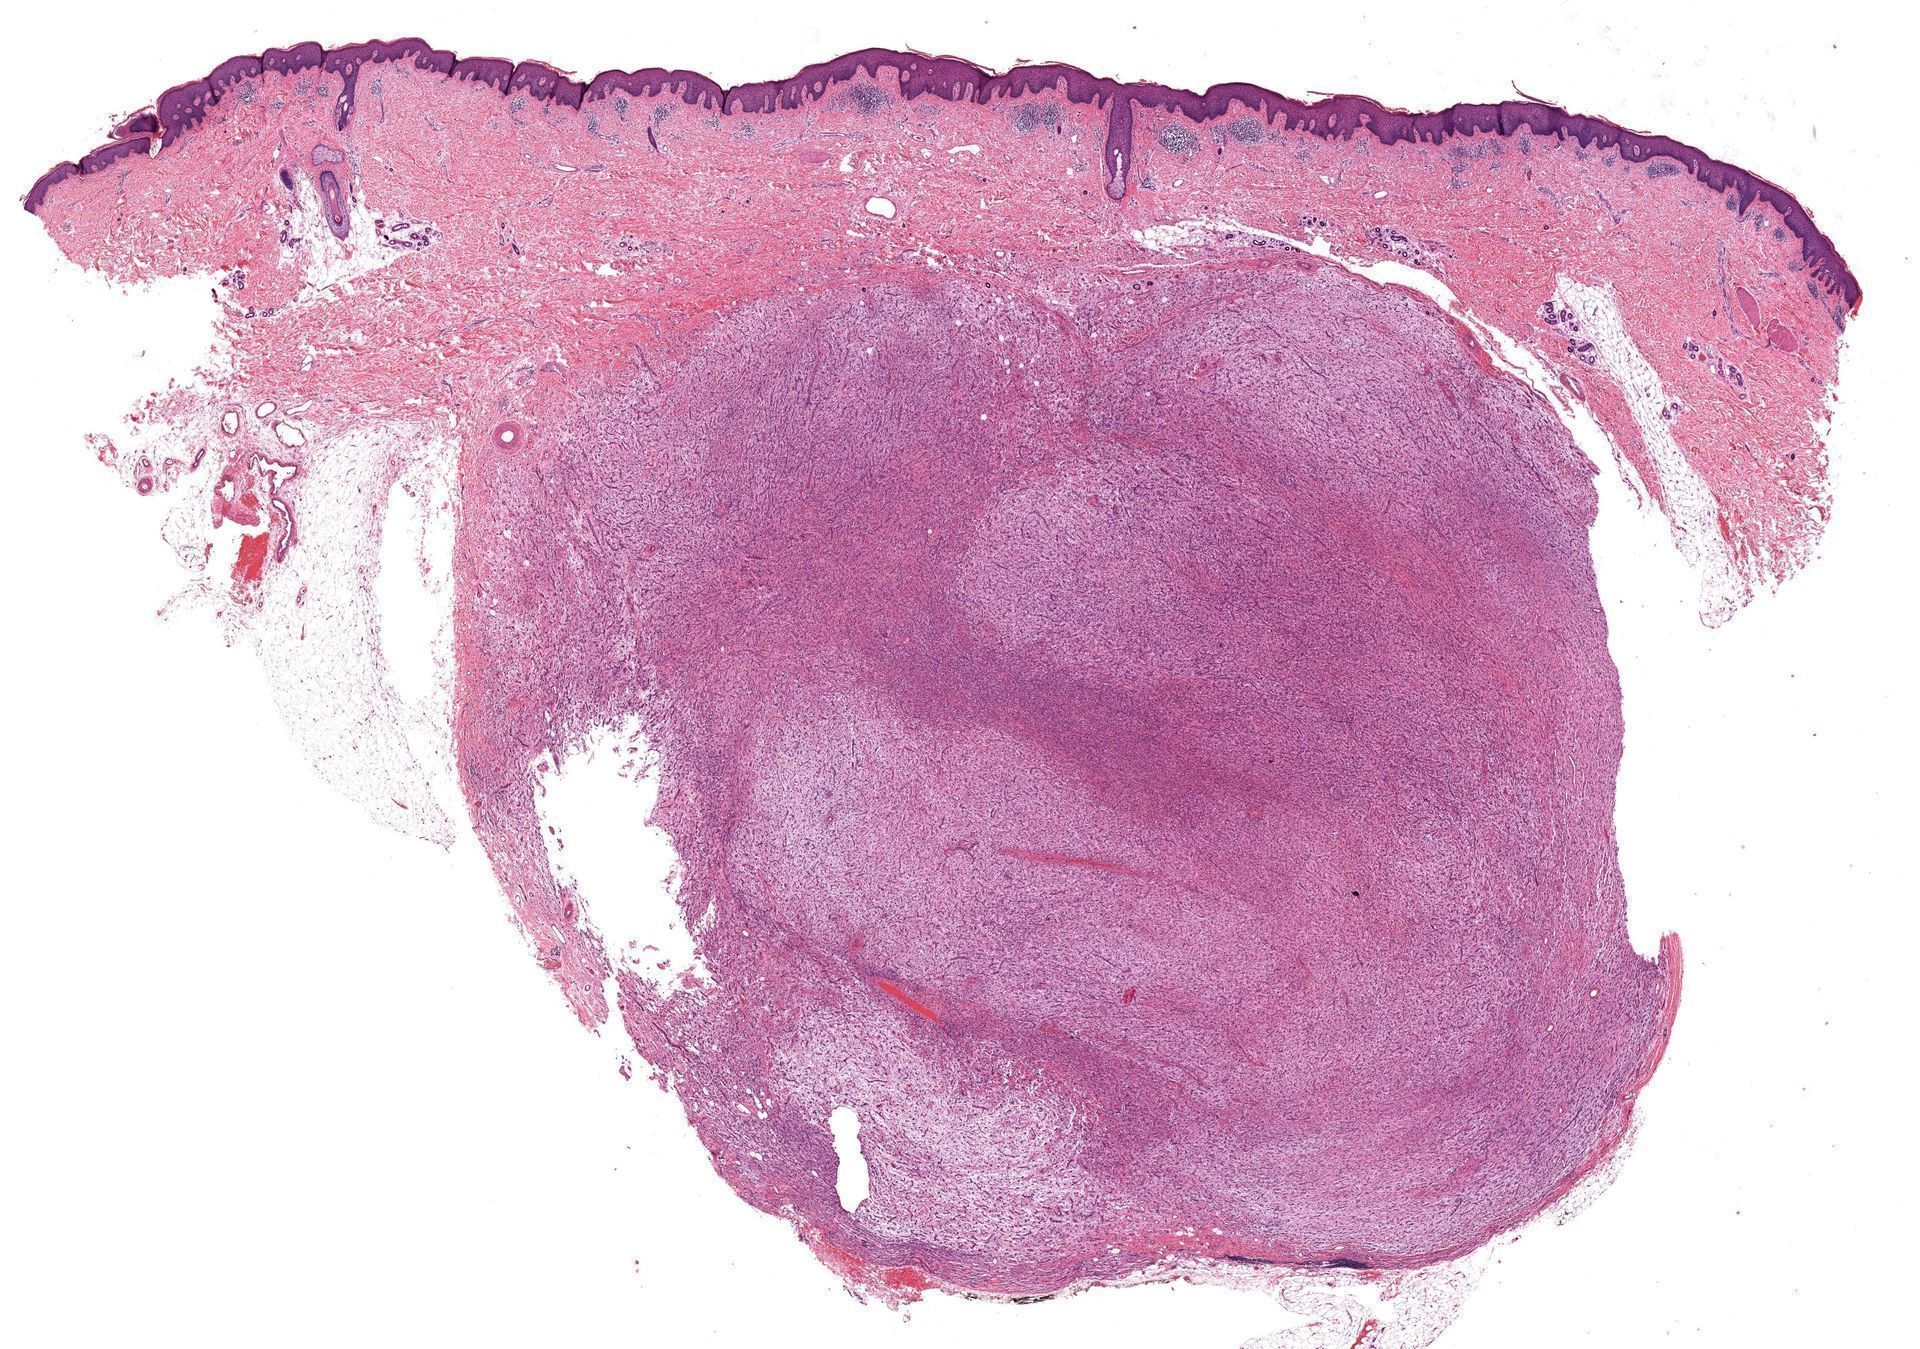

What process is happening here? How old is this patient?